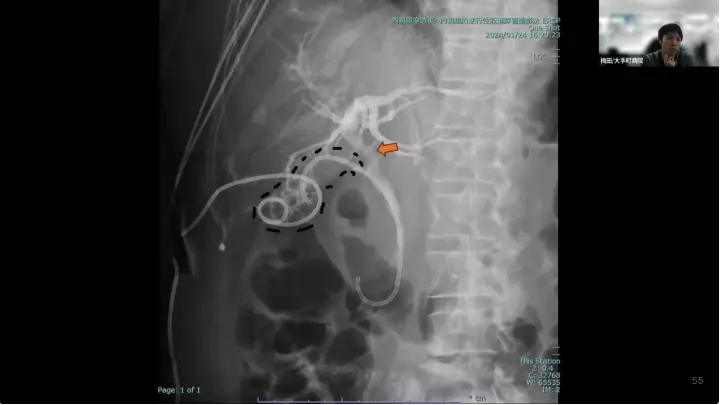

外科医目線の~急性胆嚢炎~治療編